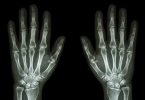

日常应注意控制体重减轻膝关节负荷,选择缓冲性好的运动鞋,避免爬山或深蹲等加重膝盖压力的动作。疼痛发作时可尝试直腿抬高锻炼股四头肌力量,每次15-20分钟,每日2-3次。若保守治疗2周无改善或出现关节变形、夜间静息痛等症状,需尽快至骨科就诊完善X线或核磁共振检查。